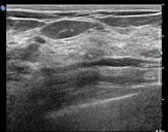

유방초음파

유방암을 진단함에 있어서 최신의 미세침 흡인세포검사, 정위적 (Stereotactic) 조직검사 및 맘모튬 조직검사를 사용하고 있으며, 그로 인해서 진단의 정확도와 절제 성공률을 높이고 있습니다. 유방암이 진단된 환자에 대해서는 외과적 유방절제술을 정확하게 시행하고 있으며, 경우에 따라 표적치료, 전신적 항암요법과 방사선 치료법 등을 동원하여 단독 혹은 병합 치료를 하고 있습니다. 유방암에서 풍부한 임상 경험과 지식을 갖고 있는 의료진들이 있으며, 각 의료진들과 긴밀한 협조를 통해 의견을 나누고 통합하는 과정을 통하여 환자에 맞는 최선의 진단과 치료를 결정합니다.